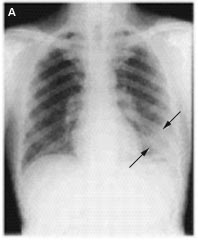

La radiografía (Rx) de tórax puede ser normal durante el pródromo febril (Fig. 2A). Sin embargo, en la fase respiratoria se puede caracterizar por infiltrado intersticial focal que se generaliza, pudiendo encontrarse áreas de consolidación en la fase tardía de SRAS Fig. 2B)(4-6).

Figuras 2A y 2B